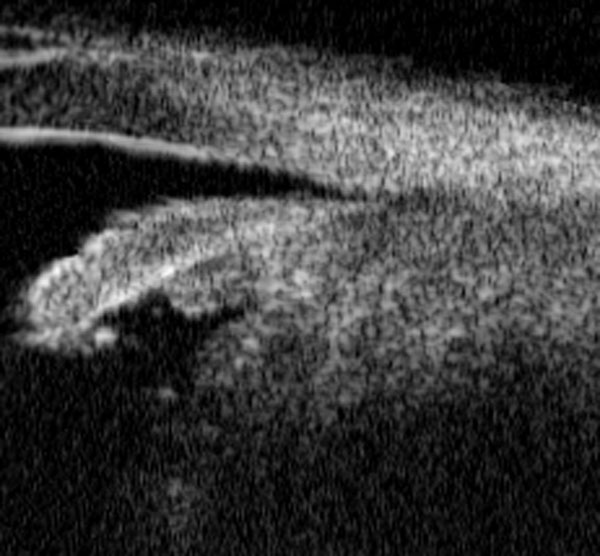

A medida que el tamaño del tumor es mayor se distorsiona el aspecto del cuerpo ciliar y no se distinguen los procesos ciliares. En ocasiones el tumor diseca la raíz del iris y entra en cámara anterior y la BMU posibilita ver como el tumor se abre paso de la cámara posterior a la anterior (FIGS 6.25.b, 6.26.b y 6.27.b). Otras veces se evidencia una infiltración de la cara posterior del iris oculta a la exploración óptica. También confirma la existencia del desplazamiento del cristalino y la opacificación del mismo (FIGS 6.28.b y 6.29.a).

F06_29_1.jpg (57063 bytes)

FIGURA 6.29.a: Un corte de BMU a nivel pupilar muestra una masa que crece tras el iris (I) infiltrando su cara posterior y empujándolo hacia adelante. El cristalino (C) está desplazado hacia atrás (flecha). (I.N.G.O.)

F06_29_2.jpg (30840 bytes)

FIGURA 6.29.b: Corte radial de BMU (composición de imágenes). La masa tiene una reflectividad media-alta con atenuación ecogénica posterior. Ocupa el cuerpo ciliar (EE: Espolón escleral), y coroides periférica y penetra en cámara anterior infiltrando la cara posterior del iris. En su límite posterior presenta aspecto pediculado y se aprecia el cuello (flecha de izquierda) y una amplia base de implantación (flecha derecha). No es posible detectar el límite profundo del tumor porque rebasa la penetración de la BMU.

Se decidió la enucleación ojo. La anatomía patológica confirmó el diagnóstico de melanoma de cuerpo ciliar. (I.N.G.O.)

La información aportada por la BMU sobre la profundidad del tumor y sobre sus límites posteriores es muy importante para la planificación del tratamiento8,9. Si por el pequeño tamaño del tumor se decide no actuar, los controles periódicos con BMU permitirán conocer si el tumor crece o se mantiene estacionario (FIGS 6.25.b y 6.25.d). Si el tamaño es compatible con el abordaje quirúrgico (ciclectomía) la BMU permitirá situar las incisiones en el lugar adecuado. Asimismo, en el postoperatorio inmediato demostrará si la extirpación ha sido completa o si persisten restos tumorales y a medio y largo plazo permitirá controlar la aparición de recidivas (FIG 6.27.f). Cuando la BMU demuestra un tamaño tal que la ciclectomía es impracticable esa información será útil para justificar la enucleación del globo (FIGS 6.28.b y 6.29.b).